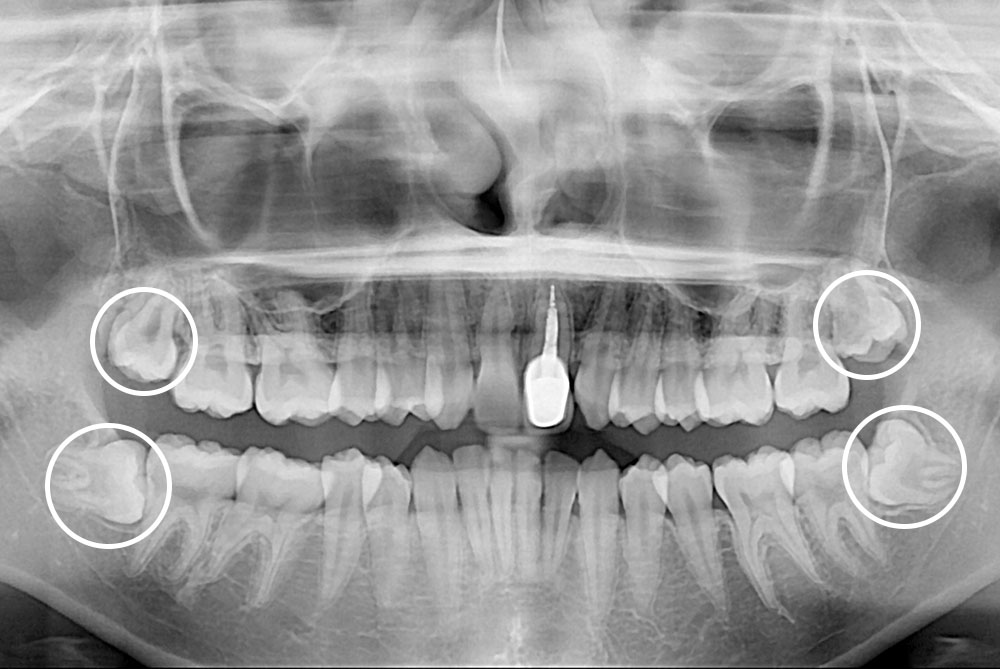

[사랑니] 매복 사랑니 발치

치료후 : 2021-03-03